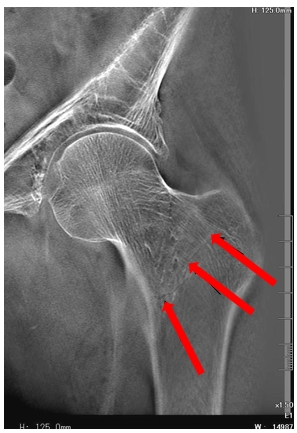

病例三:男,85岁。左髋摔伤6小时。

患者具有严重的骨质疏松,断层融合能够清晰的显示骨小梁不连续的情况,对诊断有很大的帮助。